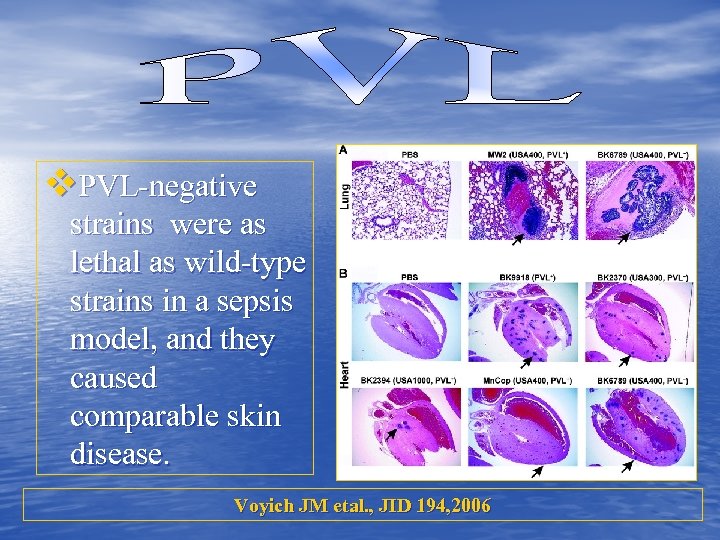

• Is it the Major Virulence Determinant in C-MRSA Disease? • Mouse infection models: PVL-positive versus PVLnegative • Strains lacking PVL were as virulent in mouse sepsis and abscess models as those containing the leukotoxin. Voyich JM etal. , JID 194, 2006

• Is it the Major Virulence Determinant in C-MRSA Disease? • Mouse infection models: PVL-positive versus PVLnegative • Strains lacking PVL were as virulent in mouse sepsis and abscess models as those containing the leukotoxin. Voyich JM etal. , JID 194, 2006

v. PVL-negative strains were as lethal as wild-type strains in a sepsis model, and they caused comparable skin disease. Voyich JM etal. , JID 194, 2006

v. PVL-negative strains were as lethal as wild-type strains in a sepsis model, and they caused comparable skin disease. Voyich JM etal. , JID 194, 2006